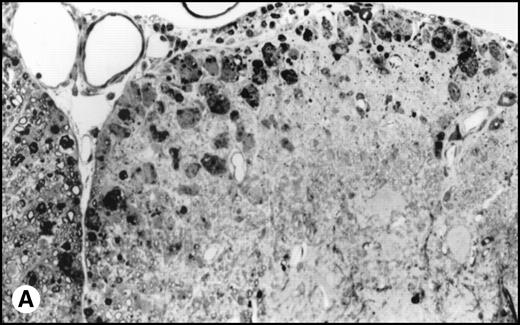

(A) Histology of SJL/J spinal cords from mice infected with TMEV. Section of spinal cord of an SJL/J mouse, 130 days after infection with TMEV. The right anterior column is completely demyelinated and numerous large lipid-laden macrophages are present close to the central sulcus. The gray uniform background reflects conspicuous gliosis in the demyelinated area (1-μm–thick, Epon-embedded section, stained with toluidine blue; original magnification × 220). (B) Section from spinal cord of an SJL/J mouse 130 days after infection with TMEV and after treatment with radiation and BMT. Inflammatory cells are still around the large venule in the parenchyma of the left anterior column, indicating active disease, but many axons are still surrounded by myelin sheaths and gliosis is less prominent (1-μm–thick, Epon-embedded section, stained with toluidine blue; original magnification × 220).